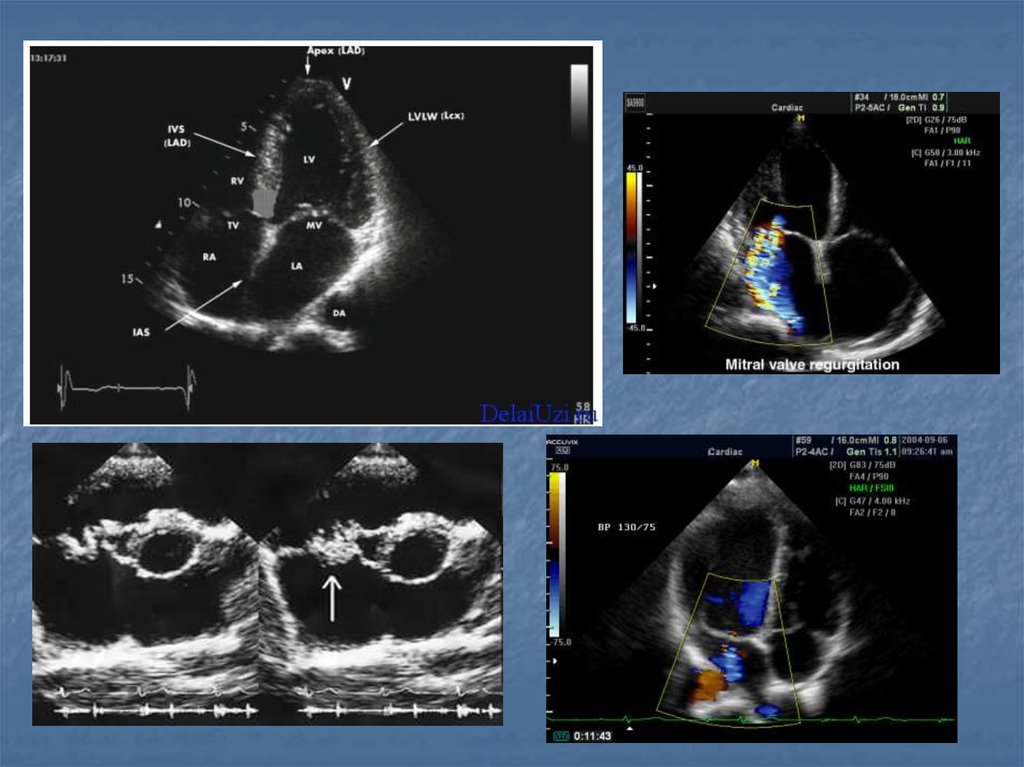

36. Показания

Воспалительные заболевания брюшной полости,

малого таза и шеи…

Наличие жидкости в брюшной и грудной полостях, в

суставах

Визуализация мягких тканей(мышцы, связки,

околосуставные пространства)

Желчекаменная, почечнокаменная болезни

Диагностика опухолей (молочная железа, яичники,

лимфоузлы)

Заболевания сосудов(варикозная болезнь,

эндортереит, оартиты, аневризмы, ангиопатия)

Врожденные и воспалительные заболевания

сердца(пороки клапанного аппарата, дефекты

стенок, нарушение функции миокарда, эндокардит,

перикардит)